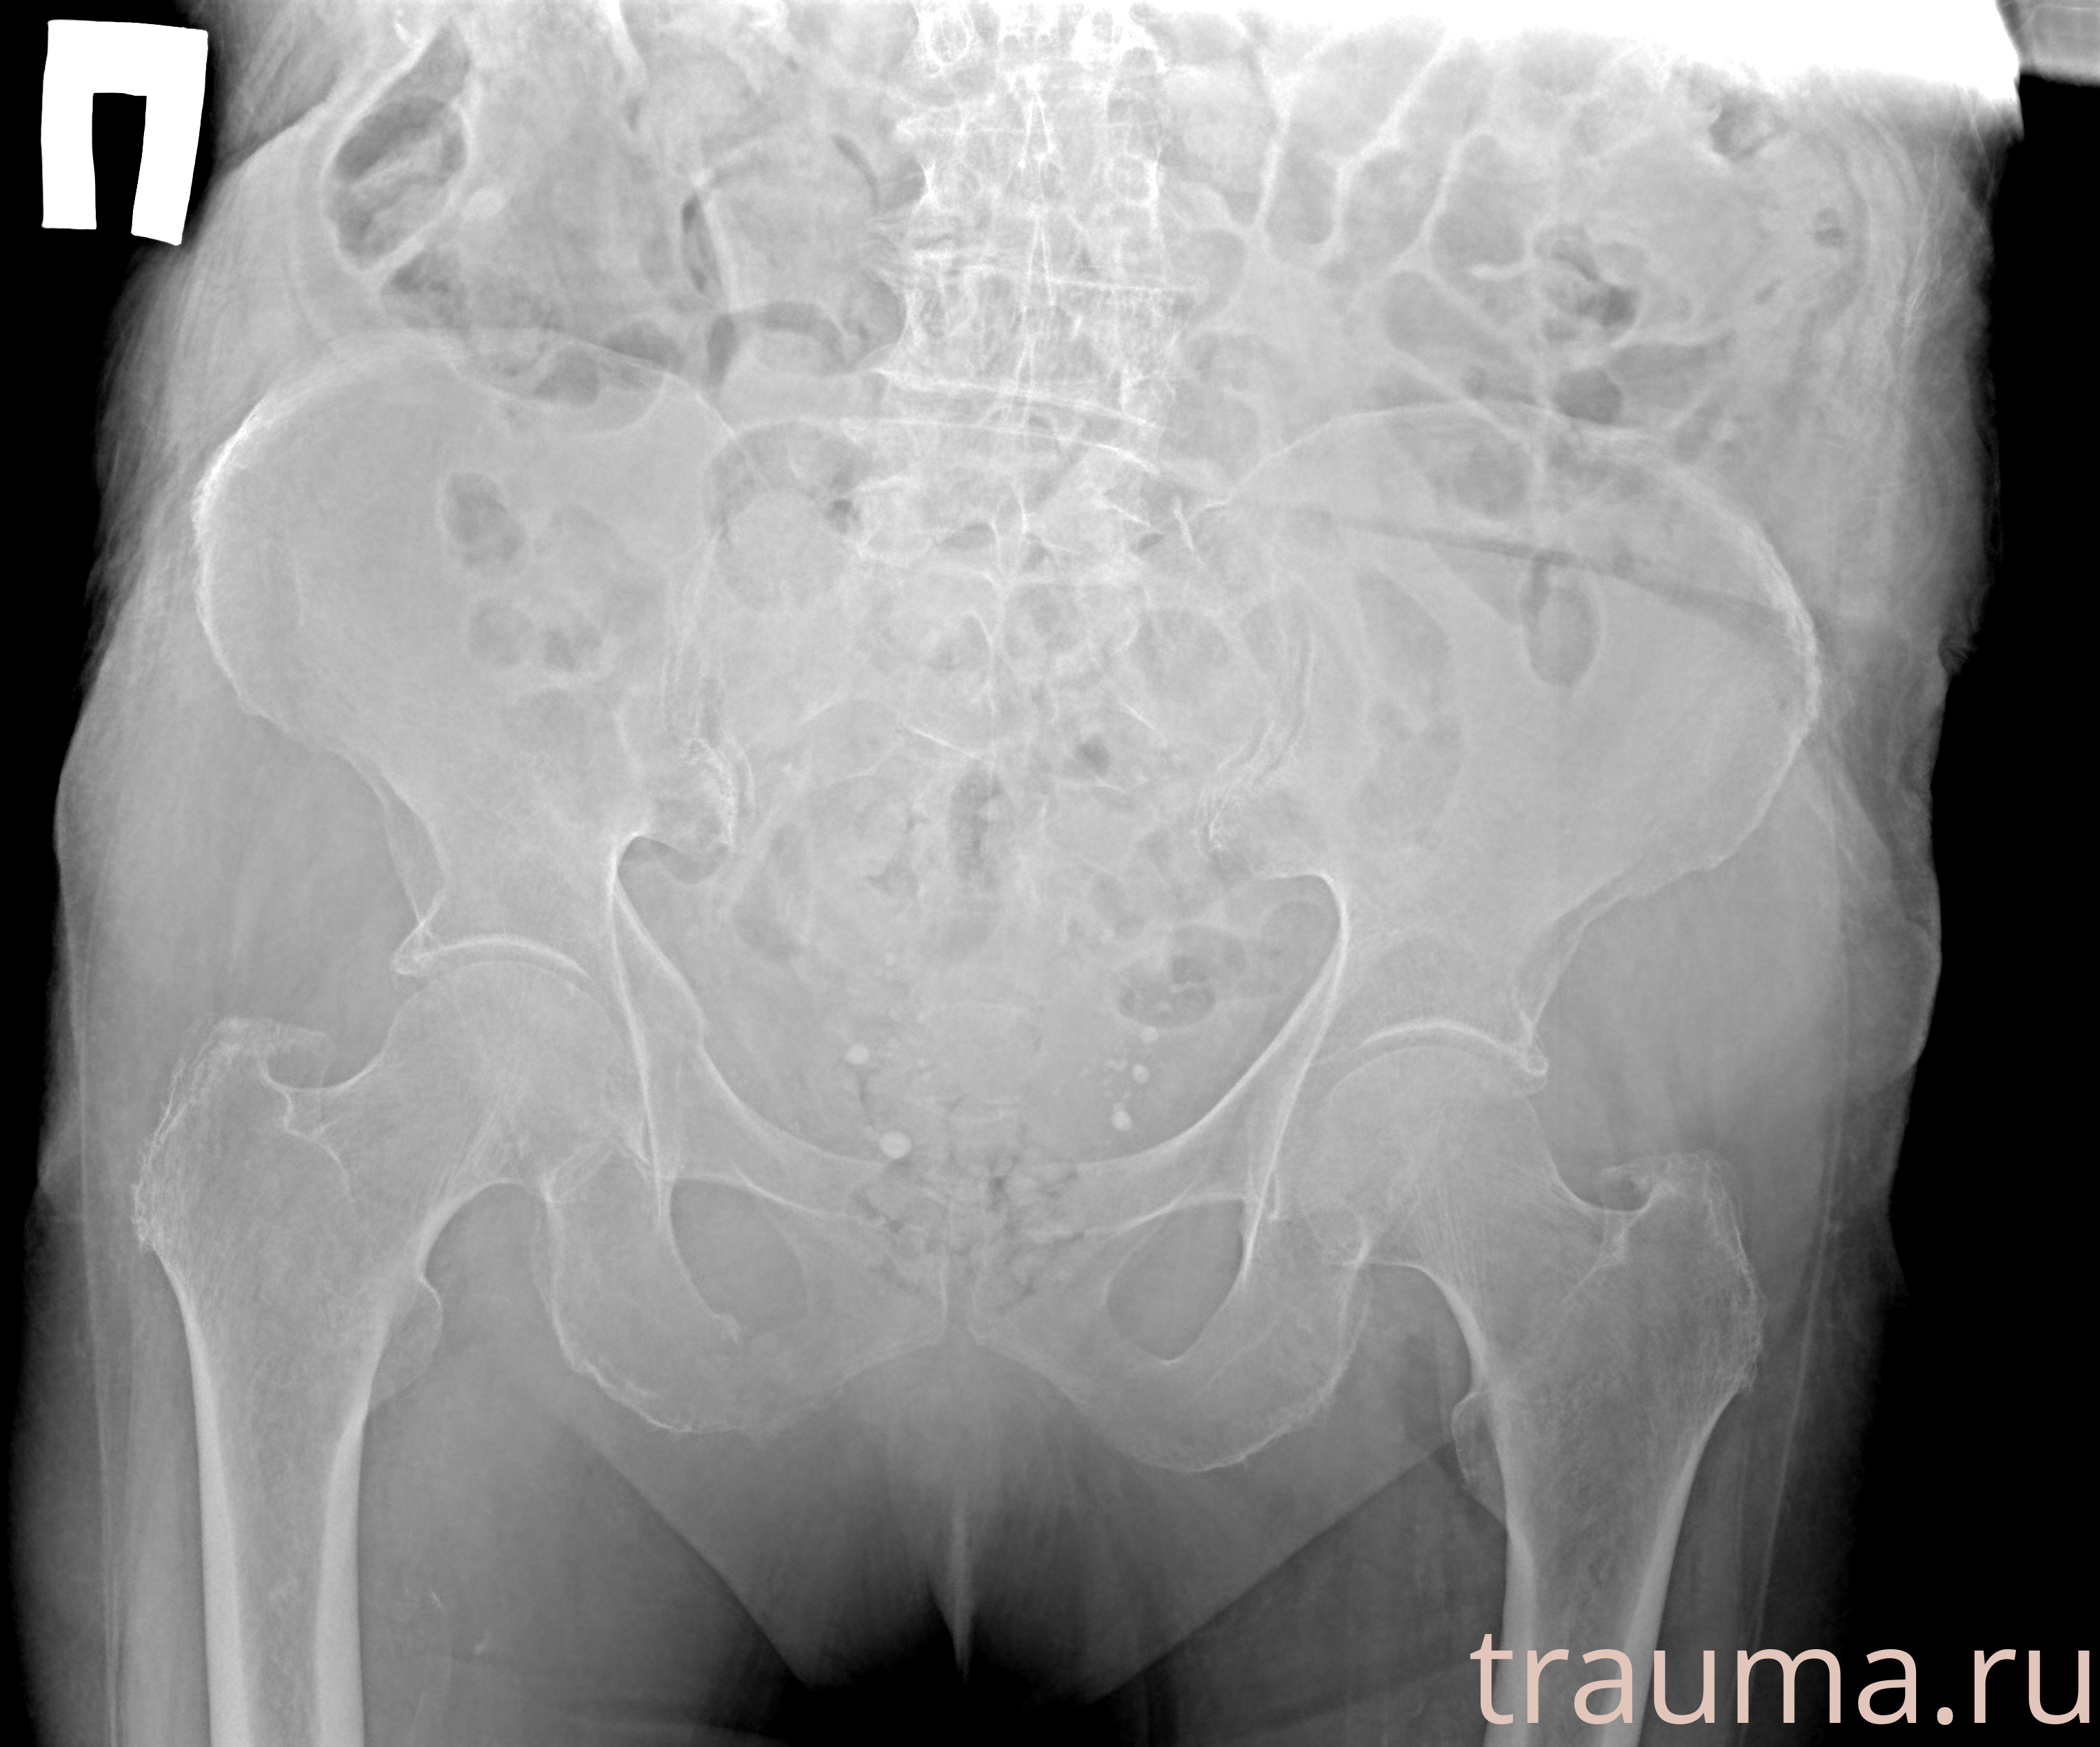

при переломе шейки бедра и пневмонии от компании МосРентген Центр - партнера Института имени Склифосовского